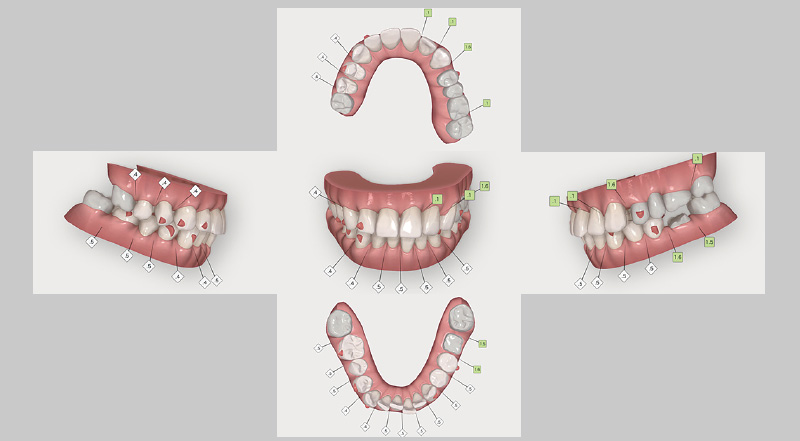

図5 インプラント埋入後に計画した、クリンチェック治療計画の矯正治療前画像。この症例では、第一大臼歯まで矯正可能な「iGo Plus」を選択。 -

図6 「iGo Plus」クリンチェック治療計画の、矯正治療後のシミュレーション画像。 -